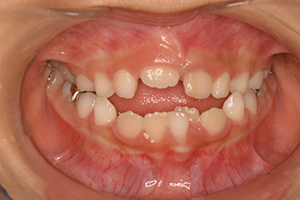

八重歯のように出てくる

レントゲン写真 治療内容・期間 2歳ちょっと前に初めて来院され、5歳にまでは定期的に虫歯のチェックや歯磨きの練習でいらっしゃっていたかたです。下の前歯2本が生え変わった段階で、歯並びが悪くなりそうでしたので矯正治療をご提案し、5歳半で矯正を開始しました。特に上顎が小さいために噛み合わせが若干逆になっています(緑の矢印...